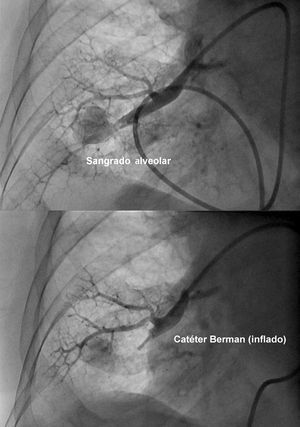

Tras un inflado del globo del catéter de Swan-Ganz, que se realizó de forma inadvertida en una rama arterial pulmonar muy periférica y por tanto de reducido calibre, de forma abrupta comenzó con hemoptisis franca. Se procedió a inflado proximal del balón del catéter «a ciegas» (en analogía al manejo de la perforación coronaria durante el intervencionismo) e intercambio del catéter de Swan-Ganz por un catéter Berman de angiografía con inyección inmediata de contraste que documentó su extravasación a parénquima pulmonar y confirmó la rotura (fig. 1, parte superior).

Fig. 1. Salida de contraste en zona de perforación (parte superior) y ausencia de paso de contraste tras inflado de balón del catéter Berman (parte inferior).

Se decidió inflar el balón del catéter Berman proximal a la rotura con control angiográfico que mostraba que no había flujo a la arteria implicada ni extravasación de contraste (fig. 1, parte inferior).